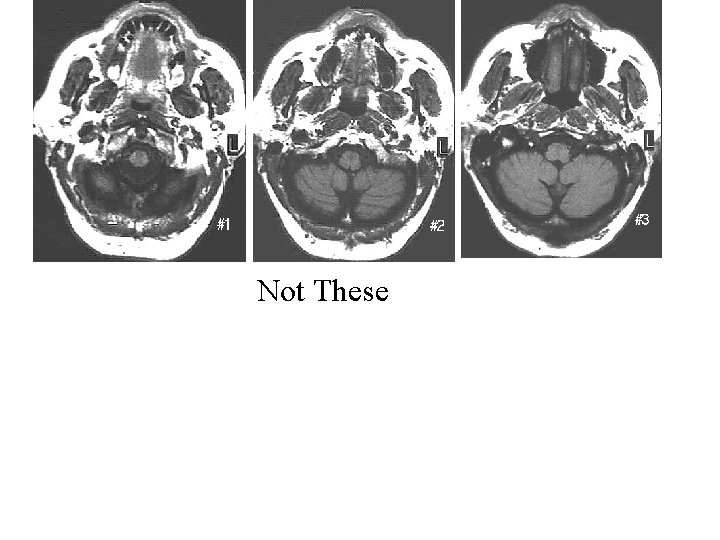

Not These